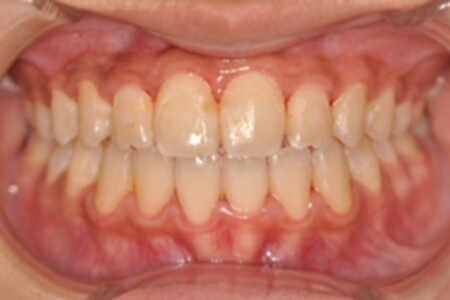

| 治療内容の詳細 | 初診時10歳の女性で、全体的ながたつきを主訴として来院されました。 検査の結果、交叉咬合を伴う、アングルⅠ級不正咬合と診断しました。 治療としては、反対咬合を改善するための装置で上顎前歯部を前方にだすと同時に上あごを広げ、セルフライゲーションブラケット装置(デーモンシステム)で歯の配列を行いました。 治療期間は2年11か月でした。 |